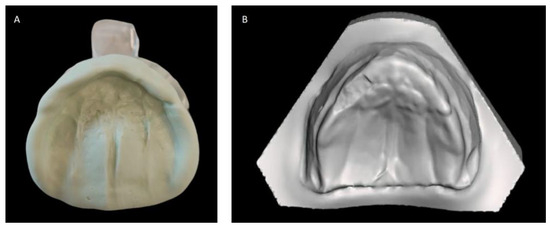

We present the rare case of an infant with HPE and CNPAS complicated by acute respiratory failure. The concomitant presence of an SMMCI was treated using a combined otorynolaringological–orthodontic approach. The multidisciplinary minimally invasive treatment involved a team comprising a neonatologist, a geneticist, a pneumologist, an ENT (ear, nose, and throat) doctor, and a pediatric dentist. The following is a detailed description of the events, the therapeutic path, and the long-term follow-up of the patient. An 8-day-old girl was admitted to the Neonatal Intensive Care Unit (TIN) of the Bambino Gesù Children’s Hospital (Rome, Italy). The baby was born at 39 weeks by caesarean section, with a birth weight of 2820 g and a length of 47.3 cm. The Apgar score was 8/10. During the clinical examination at birth, the following clinical signs were observed: cutaneous syndactyly of the II-III toes bilaterally, hypotelorism, low weight, and short stature. Respiratory distress and cyanosis ensued after a few hours. The patient was ventilated with neo-puff without much benefit. The infant was then administered CPAP (continuous positive airway pressure) and was intubated on the second day of life due to the worsening of her overall condition. Brain and facial mass MRI (magnetic resonance imaging) were performed at the birth hospital, revealing a congenital nasal pyriform aperture stenosis and the presence of a solitary median maxillary central incisor. On the eighth day of life, the patient was referred to the Bambino Gesù Children’s Research Hospital where she underwent the following tests: abdominal ultrasound, eye examination with negative results, GH, FSH, LH, cortisol, thyroid hormones, and ACTH levels, the results of which were all in the normal range. The infant also underwent an echocardiogram, which showed evidence of pervious foramen ovale. After evaluation at the Medical Genetics Department, molecular analysis showed a heterozygous variant of the GLI2 gene, for holoprosencephaly, which is classified as a class IV variant arising de novo, and which was absent in the DNA extracted from the blood of the parents. Pathogenetic variants of the GLI2 gene are associated with an autosomal dominant form of holoprosencephaly (HOLOPROSENCEPHALY 9; OMIM # 610829) with variable phenotypic expression and, in some cases, incomplete penetrance [14]. The infant was then evaluated by the ENT doctor, who performed a nasal endoscopy using a flexible laryngoscope under general anesthesia, which revealed the presence of mesenchymal bridges obstructing the right nasal cavity and a left-convex dislocation of the nasal septum. After this evaluation, the ENT doctor decided to proceed with the lysis of mesenchymal bridges, and subsequently a gentle dilation of the nasal cavities (Hegar of increasing caliber up to 4) was performed. After the widening of the nasal cavities, stabilization was achieved through balloon dilation, and two trans-nasal stents with small calibers (2.5 in one nasal cavity and 3 in the other) were placed. The infant was simultaneously evaluated by a pediatric dentist who specialized in orthodontics. The dentist found evidence of the following clinical signs: the palate had a markedly ogival shape, with growth in the direction of the anterior vertex; the median raphe palatine was severely depressed; and there was a reduction in the transverse diameters of the upper jaw. In the operating room, the dental team took an impression of the palate with addition silicone in order to create an intraoral device (Figure 1). After the surgery, given the presence of the characteristic palatal deformity, a decision was made to increase the respiratory space by applying a device. On the same day, a neonatal palatal expander plate (NPEP) [13] was built by a dental technician and positioned in the upper arch (Figure 2). The device was a mucous anchoring plate made of acrylic resin, which was extended buccally with flanges to ensure good retention [13]. A screw was placed at the center of device, to correspond with the palate median suture. To avoid any risk of suffocation, the team inserted a safety wire through two holes in the canine region. The safety wire was a surgical silk suture thread (without a needle) of approximately 70 cm in length. The orthopedic maxillary expansion therapy was initiated in order to favor the distraction of the palate at the level of the median palatine suture and assist the nasal dilation. A precise protocol for the use of the orthodontic device was established, and the child responded very well. The saturation and frequency remained regular during the insertion maneuvers, and the child kept the device in her mouth throughout the procedure. We recommend activating the central screw of the device 24 h after insertion (Figure 3). In this case, for the first day, the infant wore the device for two hours, three times a day. On the subsequent days, the device was worn for three hours, three times a day, under the constant supervision of the parents or caregivers. Immediately after the insertion of the device, the patient started swallowing and sucking normally, demonstrating that the physiological sucking–swallowing mechanism had been activated. Five days after surgery, the stents were removed and the girl was able to breath on her own, with a few episodes of desaturation that spontaneously resolved. Subsequently, the clinical condition of the child remained stable, and the follow-up visits with the ENT specialists and the orthodontist showed positive results: she resumed spontaneous breathing with good saturation (97%), her bottle feeding was going well and she had gained weight, and a valid nasal respiratory space had been secured, which was associated with the rosy appearance of the soft tissues of the oral cavity. After 15 days, the use of the expansion device was suspended and the patient was discharged. The patient underwent follow-up visits once a month for the first six months and thereafter every six months for the monitoring of respiratory function and airway patency, dental eruption, the stability and health of the median maxillary central incisor, and the growth of the jaw complex (Figure 4).

Figure 1. Dental impression of the maxillary arch in addition silicone material (A) and derived virtual plaster model (B).